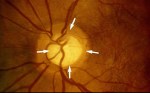

Thick corneas